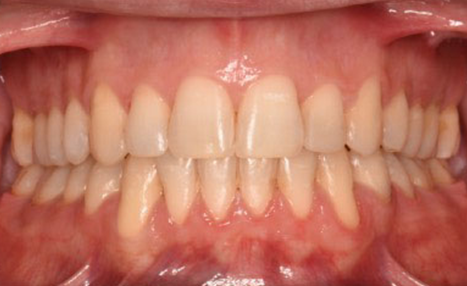

After 16 months of treatment, the transformation was evident:

(Image: 2 years after finishing)

This case demonstrates how precision in bracket placement and variable torque selection with Damon Ultima can fundamentally influence treatment efficiency and outcomes. By addressing torque control and smile arc from the very first appointment, round-tripping was minimized, biomechanics were optimized, and finishing required only fine adjustments rather than compensations.

The Damon Ultima system allowed the clinician to align facial esthetics, occlusal function, and long-term stability in a challenging adult case, underscoring the value of intentional planning and execution.

Orthodontic success depends not only on wire sequences or finishing mechanics but on the strategic decisions made at the bonding appointment. In this case, Damon Ultima provided the control necessary to achieve predictable, efficient, and esthetically pleasing results.